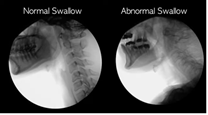

La Disfagia es la dificultad o sensación de tener dificultades para tragar ciertos alimentos, líquidos, medicamentos o saliva.

Las dificultades pueden darse en cualquiera de las tres fases de la deglución. Se pueden clasificar según la localización de las mismas.

| Ir al vídeo: Videofluoroscopia de la disfagia (Ianessa humbert, 2020) |